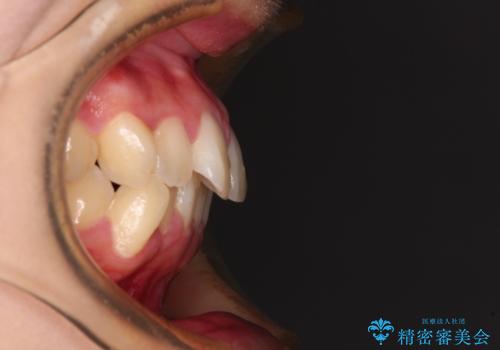

- 口元の閉じにくさを気にして来院された患者様です。

上下ともに歯列が前方に突出していたため、上下左右の第一小臼歯4本を抜去し、ワイヤー装置による矯正治療を行うこととしました。

舌の突出癖による影響もあったため、舌のトレーニングを並行して実施しました。